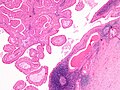

Warthin tumour

- AKA papillary cystadenoma lymphomatosum.

Cytology

Features:[9]

- Oncocytes.

- Well-defined cell border.

- Granular cytoplasm.

- Nucleoli.

- Oncocytes are often associated with mast cells, i.e. on "top of" oncocytes.

- Mast cells: very granular dark staining cytoplasm (on smears).

- Lymphocytes.

- Necrotic material (cyst contents).

DDx:

- Acinic cell carcinoma.

- Spacing of tumour in AcCC is more irregular and appear more crowded.

- The cell borders in AcCC is less obvious.

- Oncocytoma.

- Oncocytoma (vis-a-vis Warthin tumour) has more cells, more cytoplasm, more granularity of cytoplasm, more complex architecture.[3]